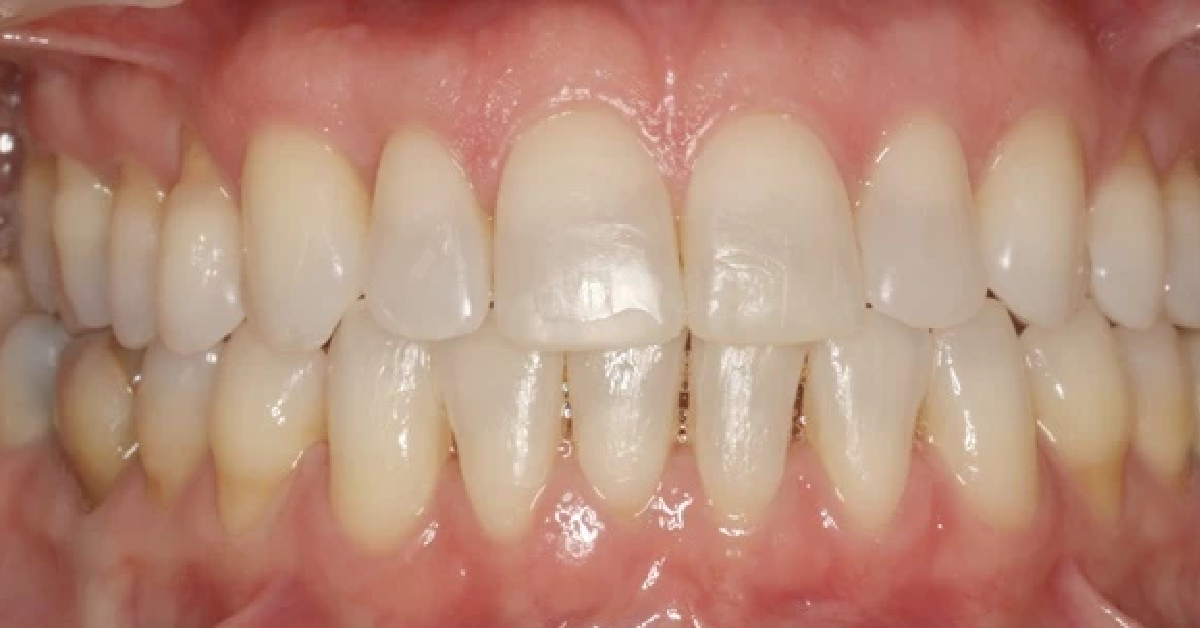

Vårt arbeid

Alle pasienter som vises har gitt skriftlig samtykke til at bildene kan brukes på klinikkens nettside.

Ønsker du en vurdering av behov for tannregulering, kan du ta kontakt med klinikken for time til konsultasjon.